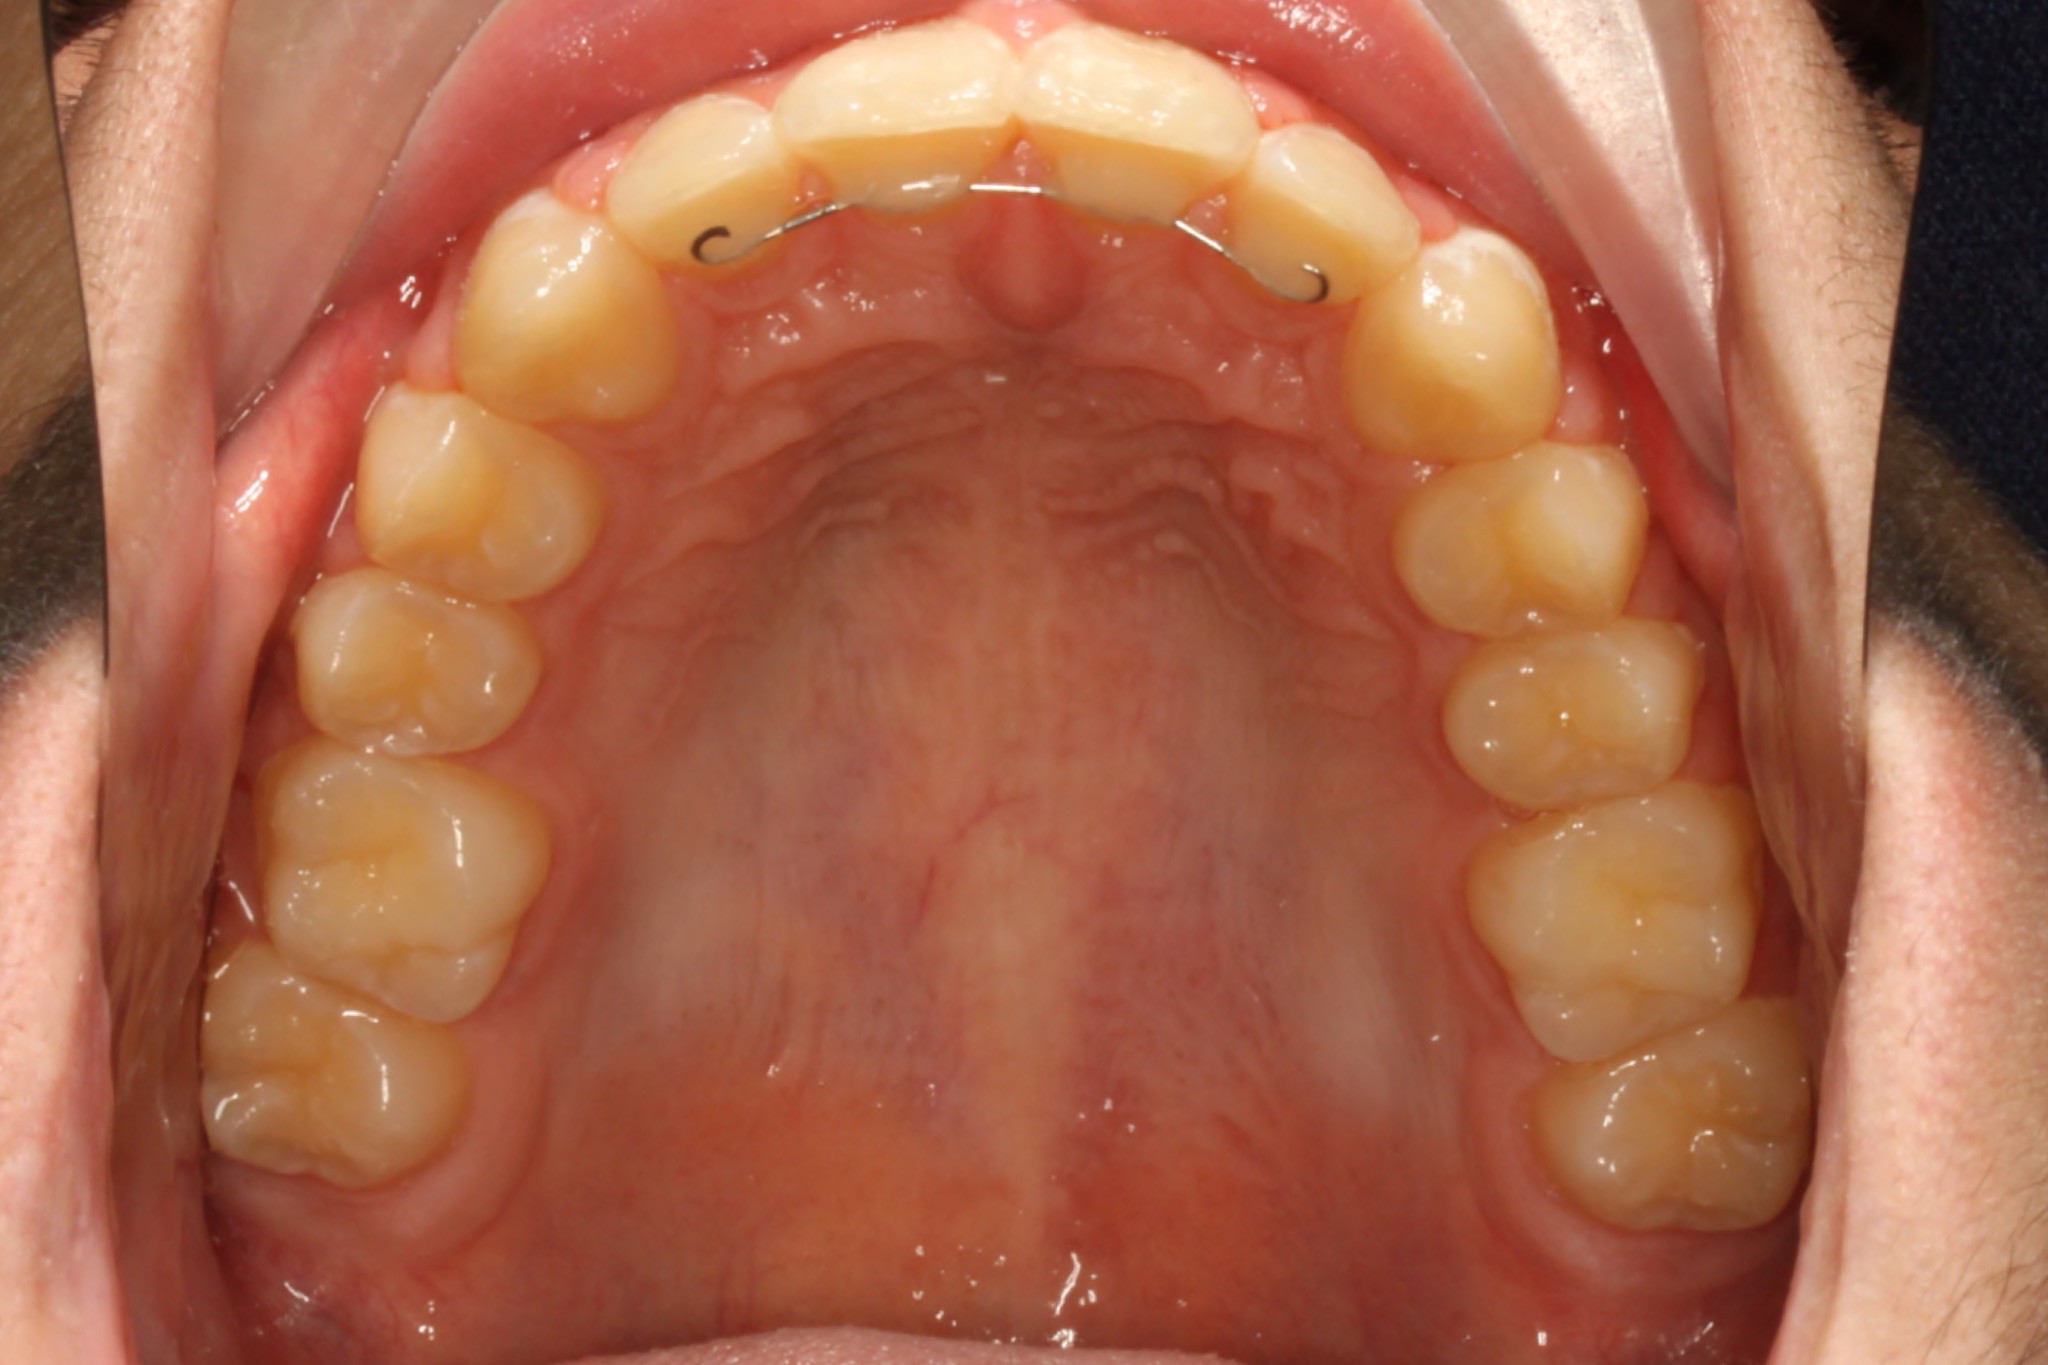

Traditional Braces Old Bridge, NJ Family Orthodontics KidZdent Medicaid Braces Nj Otherwise, you can look at programs offered by. You may be able to get free braces from medicaid if your dental problems are causing health problems that can be fixed with braces. Medicaid is the primary third party,. Nj familycare/medicaid is new jersey’s public health care coverage program. Prior authorization may be needed for increased. If you qualify for medicaid. Medicaid Braces Nj.